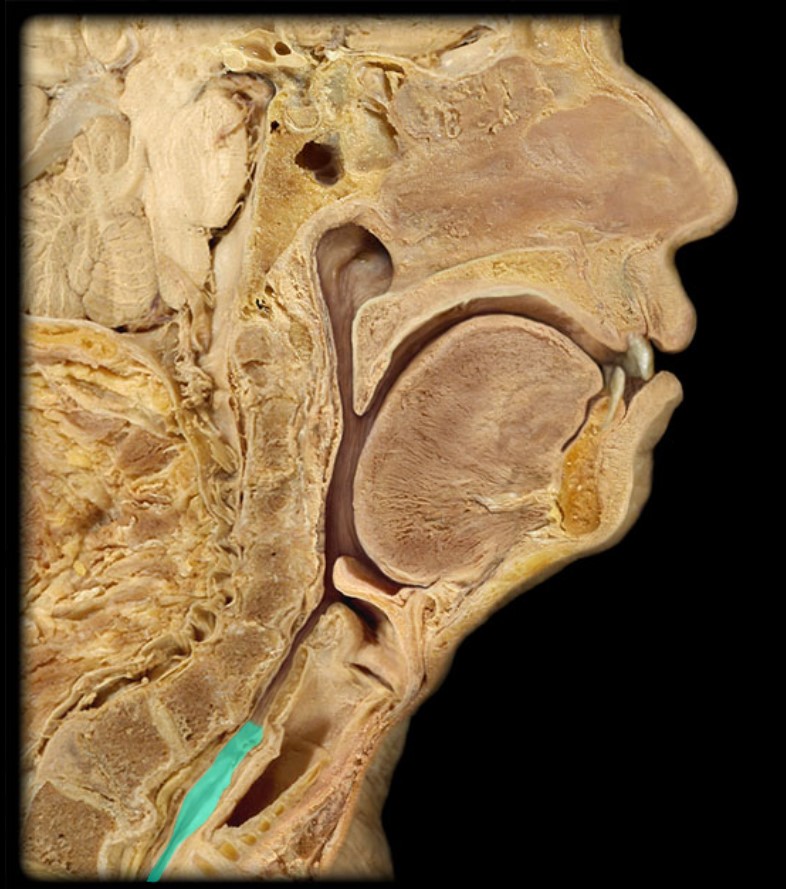

Anatomy 5 - Bifurcated Skull

29 Terms

1

New cards

Thyroid Gland

(Donor Only)

2

New cards

Atlas

3

New cards

Vertebral Artery

(Donor Only)

4

New cards

Nasal Septum

(Donor Only)

5

New cards

Esophagus

6

New cards

Trachea

7

New cards

Vocal Fold

8

New cards

Epiglottis

9

New cards

Hyoid

10

New cards

Mandible

11

New cards

Mylohyoid

12

New cards

Geniohyoid

13

New cards

Genioglossus

14

New cards

Lingual Tonsil

15

New cards

Palatine Tonsil

16

New cards

Uvula

17

New cards

Soft Palate

18

New cards

Palatine Bone

19

New cards

Maxilla

20

New cards

Pharyngeal Tonsil

21

New cards

Auditory Hiatus

22

New cards

Torus Tubarius

23

New cards

Sphenoid Sinus

24

New cards

Inferior Nasal Concha

25

New cards

Middle Nasal Concha

26

New cards

Superior Nasal Concha

27

New cards

Nasal Vestibule

28

New cards

External Nares

29

New cards

Frontal Sinus